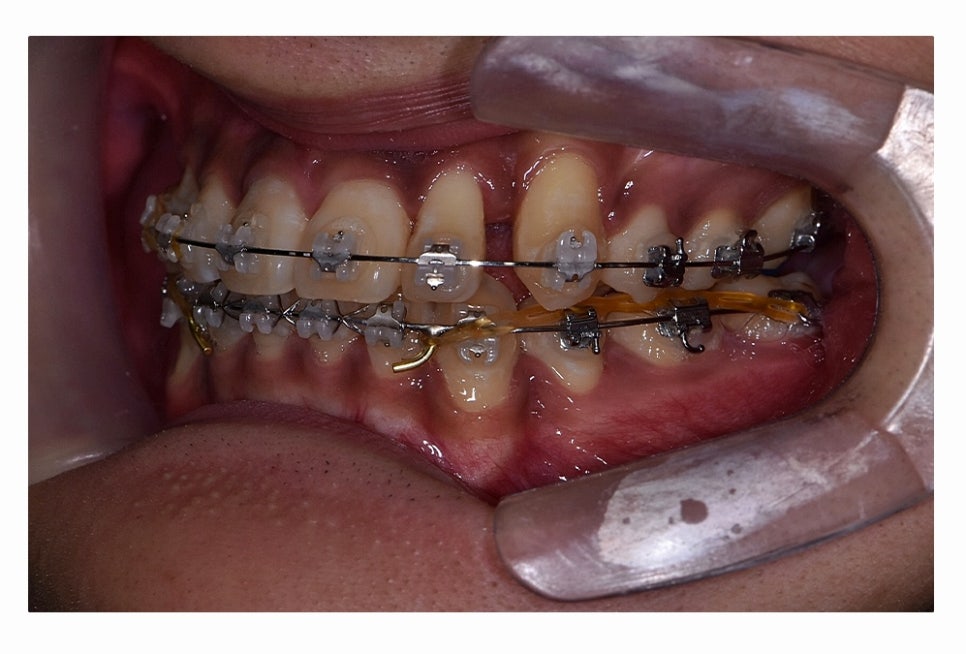

오늘 보시는 환자분의 사례처럼 덧니가 치아끼리 겹쳐 있는 경우에

치아의 이동 공간 확보를 위해서 덧니 발치 필요한 사례였으며

교합과 치아교정 후 얼굴 변화를 고려할 때도 치아교정 과정에서

발치가 필요한 사례였다고 볼 수 있어요.